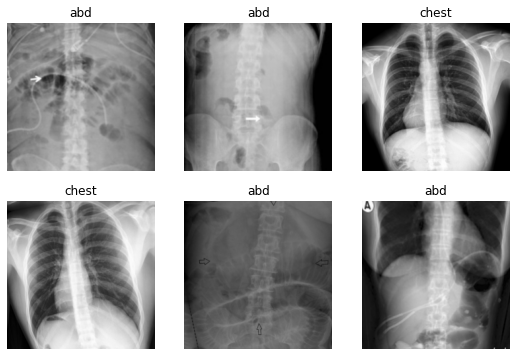

Note: When you run this next cell in Colab, a batch of data will be shown with or without augmentation transforms applied. (1) Run this cell once with the box next to

apply_transformsunchecked to see a sample of the original images. (2) Next, run the cell a few more times after checking the box next toapply_transformsto see what happens to the images when the transforms are applied.

dls = ImageDataLoaders.from_folder(path, valid='val', seed=42, item_tfms=Resize(460), batch_tfms=tfms, bs=16)

dls.show_batch(max_n=6)